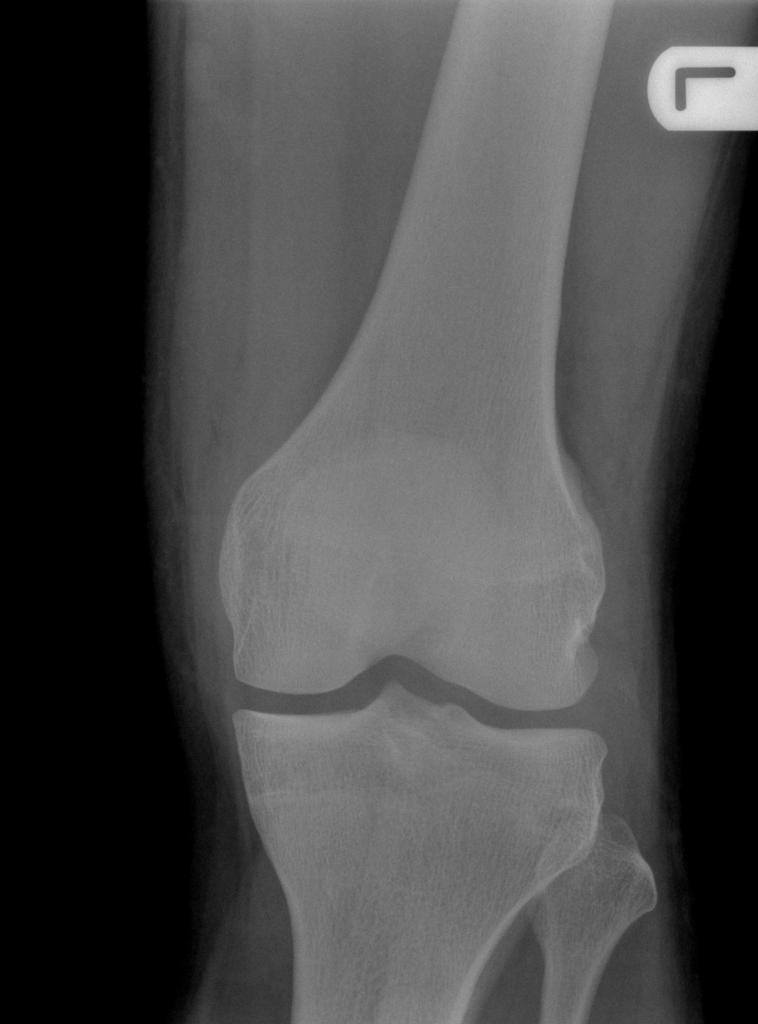

What does this x-ray show?

This is an antero-posterior radiograph of the left knee of an unknown patient taken at an unknown date. There appears to be no radiological evidence of osteoarthritis: i.e. there is no loss of joint space, osteophytes, subchondral sclerosis or subchondral cysts. There are also no visible fractures or prostheses. In summary, this is a normal radiograph of a patient’s left knee”